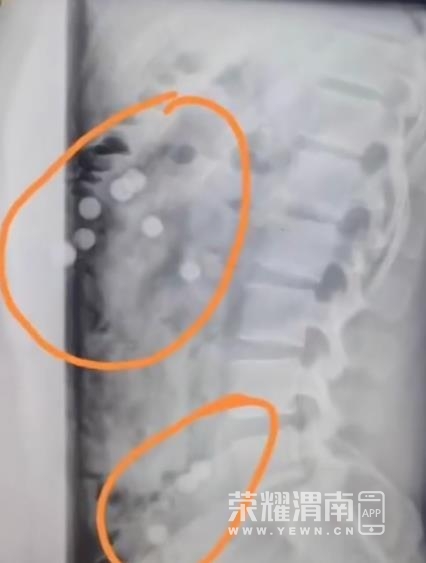

19岁小伙腰痛拍片肠胃里全是奶茶珍珠,医生都懵了

桐庐有个19岁的小伙子,因为腰不舒服去医院拍了个X光片。片子拿到手,医生都懵了,上面怎么有一颗颗的东西?再一打听,小伙子说可能是之前喝的珍珠奶茶。医生猜测这些“珍珠”是直接吞下去的,没有嚼,所以消化不了,“成年人还好一点,如果是小孩子,肠胃蠕动慢,严重的会出现肠梗阻”。